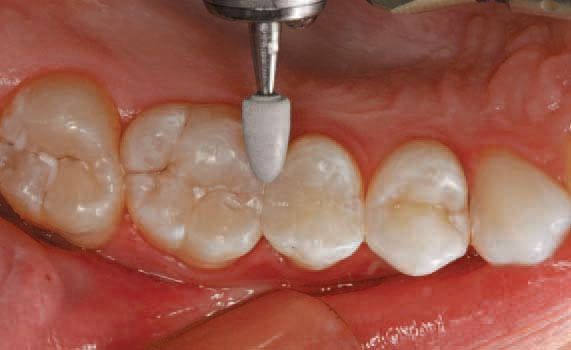

Final finishing and polishing were completed using appropriate finishers. A series of

Astropol finishing and polishing points (Ivoclar Vivadent) were used to complete the restoration. Gray finishing points were used to smooth the surface (Fig. 11).